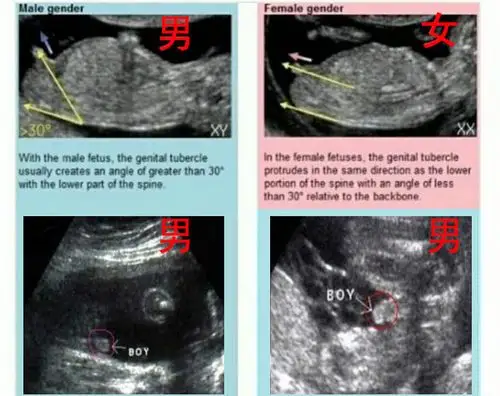

怀孕十二周可以从b超中的小肿块分辨男女,这真的可以看出来吗?

12周胎儿男女生殖图区别图片,nt检查看男女准不准?-医孕帮